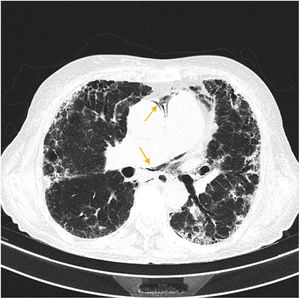

More infoA 72-year-old woman with chronic cough due to severe interstitial lung disease and fibrosis was found in a coma upon awakening. Glasgow Coma Scale score: 3. Gaze deviation to the left. Generalized hypotonia. Anisocoric pupils with right-sided mydriasis. Thoracic CT scan: small left apical pneumothorax and presence of ectopic air in the upper mediastinum (arrows) (Fig. 1). Brain CT scan: presence of numerous air bubbles located in the cerebral sulci (arrows), and cortico-subcortical hypodense areas distributed in bilateral parieto-occipital regions (Fig. 2). An intrapulmonary shunt would be mechanism involved that could explain our case (for the lack of a patent foramen ovale). A sudden increase of intrathoracic pressure due to Valsalva maneuvers, along with the development of pneumothorax and pneumomediastinum in a pathological lung could facilitate the passage of air into the pulmonary veins and from there into the left circulatory system causing cerebral air embolisms.